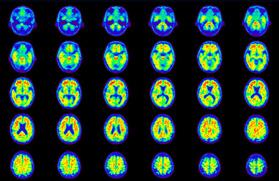

Head / Case5 : Amyloid

Axial

Courtesy : Kindai University Hospital

- Imaging protocol

- Injected dose: 4.27 MBq/kg, 18F-Flutemetamol

- Uptake time: 99 minutes

- Scan time: 20 minutes